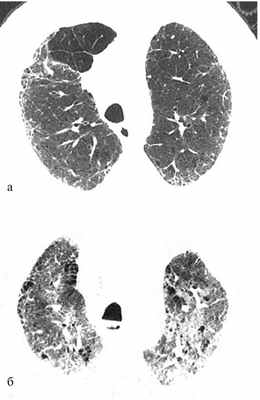

В качестве примера быстрого прогрессирования ИФЛ приводятся данные компьютерной томографии (КТ) больного в дебюте болезни (а) и через 4 мес (б) (рис. 1).

Рис. 1. КТ больного ИФЛ в дебюте болезни (а) и через 4 мес (б).